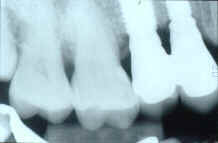

podemos apreciar el puente provisional una vez cementado en la boca del paciente, a través de las chimeneas podremos desenroscar los tornillos y retiraremos el puente provisional de la boca, así podremos comprobar que han quedado bien cementados los cilindros con la resina del provisional, eliminaremos los mínimos restos de cemento que hubieran podido quedar y procederemos a volver a roscar los tornillos y colocarlo en la boca, podemos quedarnos bien seguros que el ajuste pasivo de nuestros dos cilindros de oro es totalmente pasivo, entendiendo por ajuste pasivo la total ausencia de dolor y de tensiones a la hora de atornillar los cilindro, y comprobando que atornillando un solo cilindro, el otro también tiene un ajuste técnicamente pasivo, paso que comprobaremos realizando una radiografía después del cementado tal como podemos apreciar en la diapositiva nº 18,

gracias al espacio que hemos dejado entre los cilindros y el puente, aproximadamente unas tres micras habremos corregido cualquier posible tensión entre nuestros implantes, y sabemos que con cilindros mecanizados de origen y sin haber sido sometidos a ningún tipo de temperatura ni ningún proceso que pueda producir deformaciones o tensiones el ajuste de dichos cilindros es realmente un ajuste de lo mas técnicamente perfecto.

ya comentábamos antes que la cerámica que hemos utilizado, VITA OMEGA 900, tiene un excelente comportamiento estético en la boca del paciente, solo nos queda comprobar que los parámetros de oclusión son los correctos, en máxima intercuspidación hay contacto oclusal pero intentamos no crear interferencias oclusales con cúspides muy pronunciadas, y sobre todo que exista una perfecta protección canina en la desoclusión tal como podemos apreciar en la diapositiva nº 39, y en la diapositiva nº 40 el ultimo control de ajuste realizado radiológicamente.

Diapositivas 39, y 40. Control de la desoclusión y radiografía de control de ajuste |